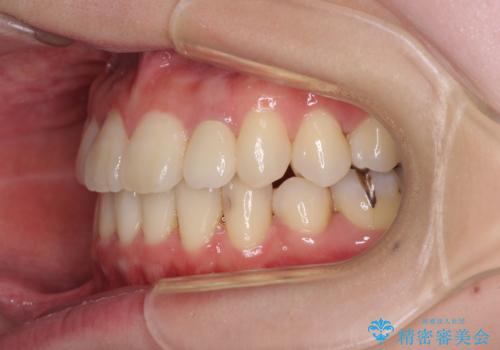

- 下顎の歯が舌側に倒れていることと、前歯の咬み合わせの不具合を気にして来院された患者様です。

受け口傾向の口元であるため、下顎左右小臼歯各1歯を抜歯して歯列を整えることとしました。

前歯には治療中の仮歯が装着されていたため、矯正治療後にオールセラミッククラウンにて補綴治療を行うこととしました。

抜歯矯正は2年から2年半程度の治療期間を要することが一般的ですが、僅か1年1ヶ月で終了しました。

あっという間に気になっていた歯並びが改善し、患者様には大変満足していただきました。